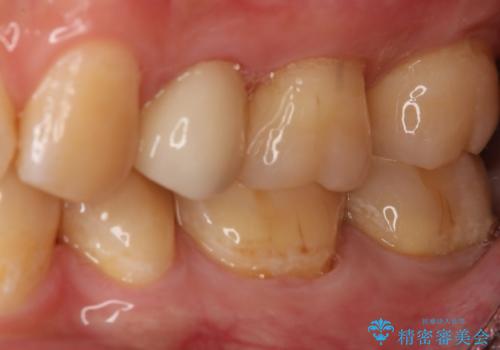

- 左下7番のCR劣化を自費治療にて希望された患者様です。

切削量を考慮してセラミックインレーでの治療を選択しました。

CR直下と隣接面にう蝕が進行していたので、除去した上で形成、印象しています。